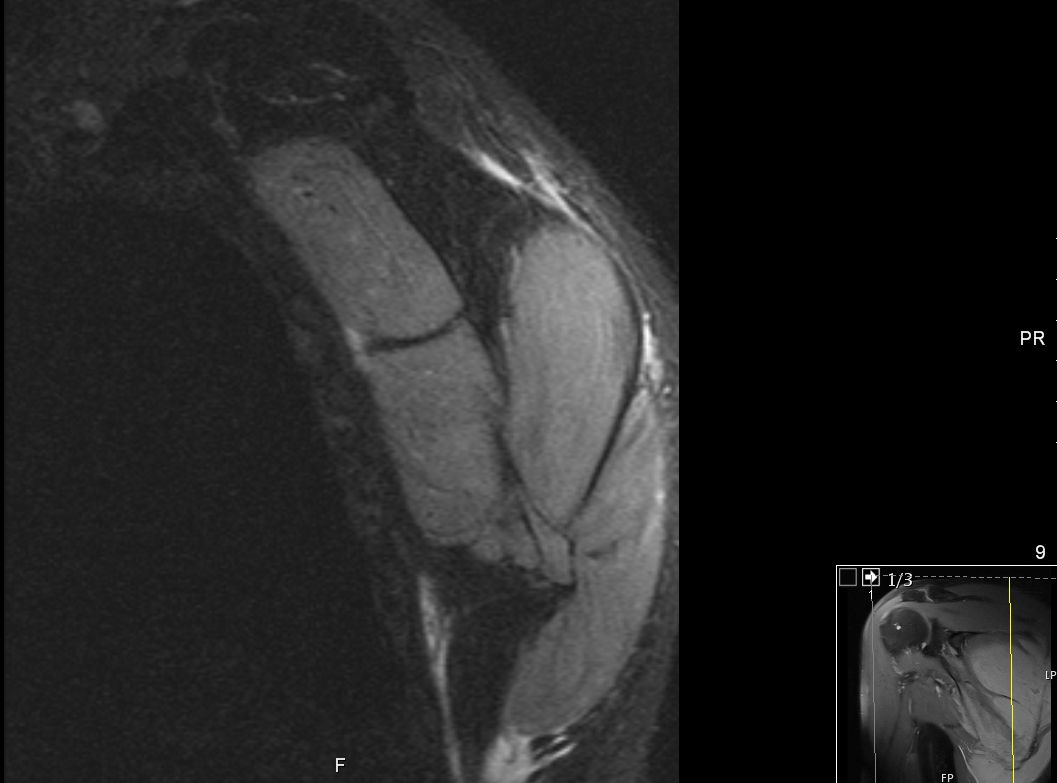

Muskelinfiltrat

63-jähriger Mann, der vor 5 Jahren eine T - Promyelozyten - Leukämie hatte. Nach ASCT bisher rezidivfrei. Jetzt beschwerden in der rechten Schulter. Das MRT zeigt intramuskuläre Raumforderungen. Die Biopsie ergab Infiltrate der APL.